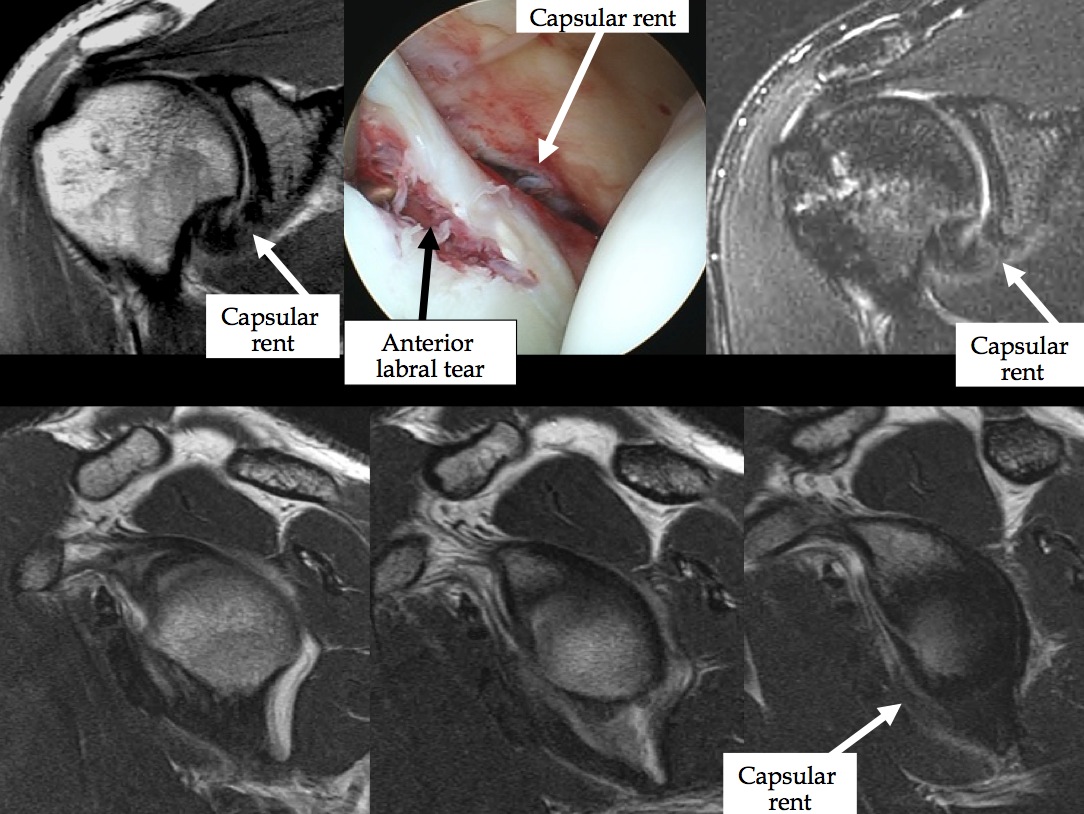

Various examples of anterior capsular injury in anterior shoulder dislocation with glenohumeral joint instability